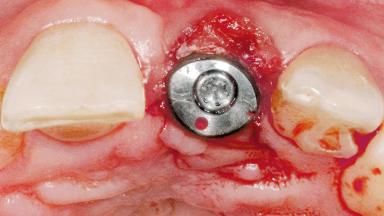

Late Flapless Placement of an Implant in a Maxillary Left Central Incisor Site

A 39-year-old male patient presented with a chief complaint of discomfort and gingival discoloration around his maxillary left central incisor. He was in good general health and was a non-smoker. His past dental history was significant because of the traumatic fracture of tooth 21 in a sporting accident at age 13. Initial dental treatment included endodontic therapy and a full-coverage restoration. The patient became symptomatic 5 years later, when structural failure of the tooth resulted in the dislodgment of the crown. Endodontic retreatment, apical surgery, and post-and-core restoration were performed.

Type of Implants One-Piece

Attachment One-Piece

Placement Protocol Early or late implant placement

Bone Volume Deficient horizontally, requiring prior grafting